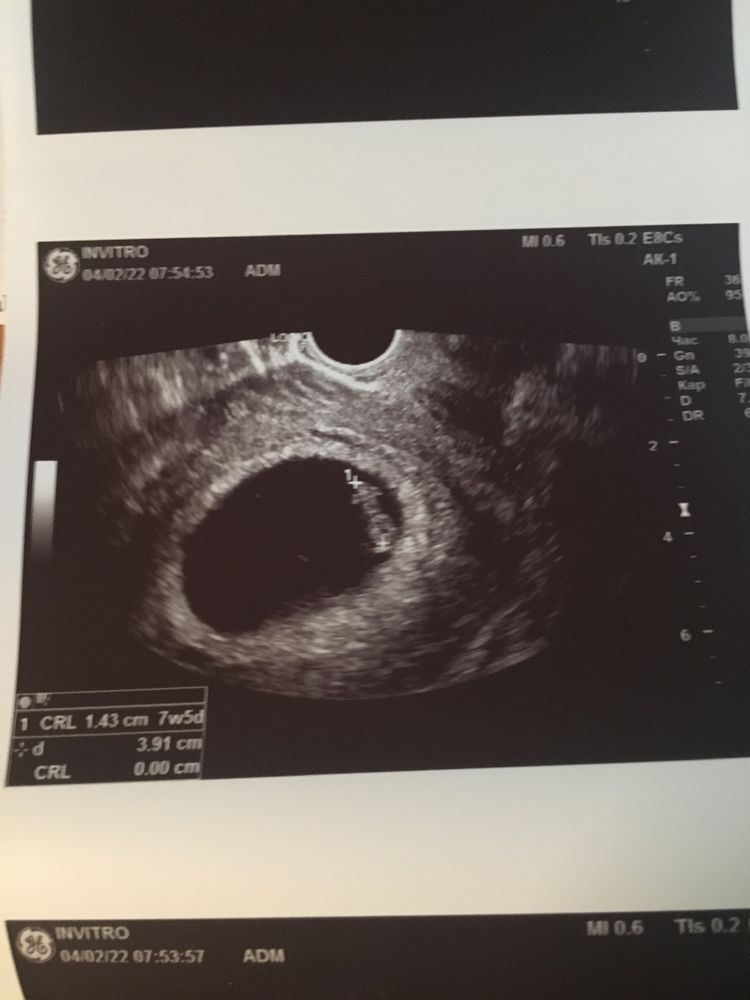

Токсикоз и усталость есть, но не все так плохо. Сходила на узи в 7+2, подтвердили маточную беременность, сказали, что есть небольшая отслойка и лучше принимать дюфастон по 2 таблетки, больше лежать. Ну это я сама виновата, поднимала уже совсем нелегкого сына. ХГЧ был высоким, но не из-за двойни, а ранней овуляции, до сих пор не понимаю, когда она у меня произошла(во время м?), срок по узи 7+5, даже больше, чем акушерский.